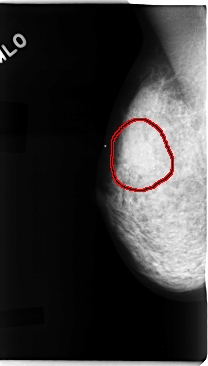

C_0092_1.RIGHT_MLO

FILE: C_0092_1.RIGHT_MLO.OVERLAY

TOTAL_ABNORMALITIES 1

ABNORMALITY 1

LESION_TYPE CALCIFICATION TYPE PLEOMORPHIC DISTRIBUTION CLUSTERED

LESION_TYPE MASS SHAPE OVAL MARGINS ILL_DEFINED

ASSESSMENT 5

SUBTLETY 5

PATHOLOGY MALIGNANT

TOTAL_OUTLINES 1